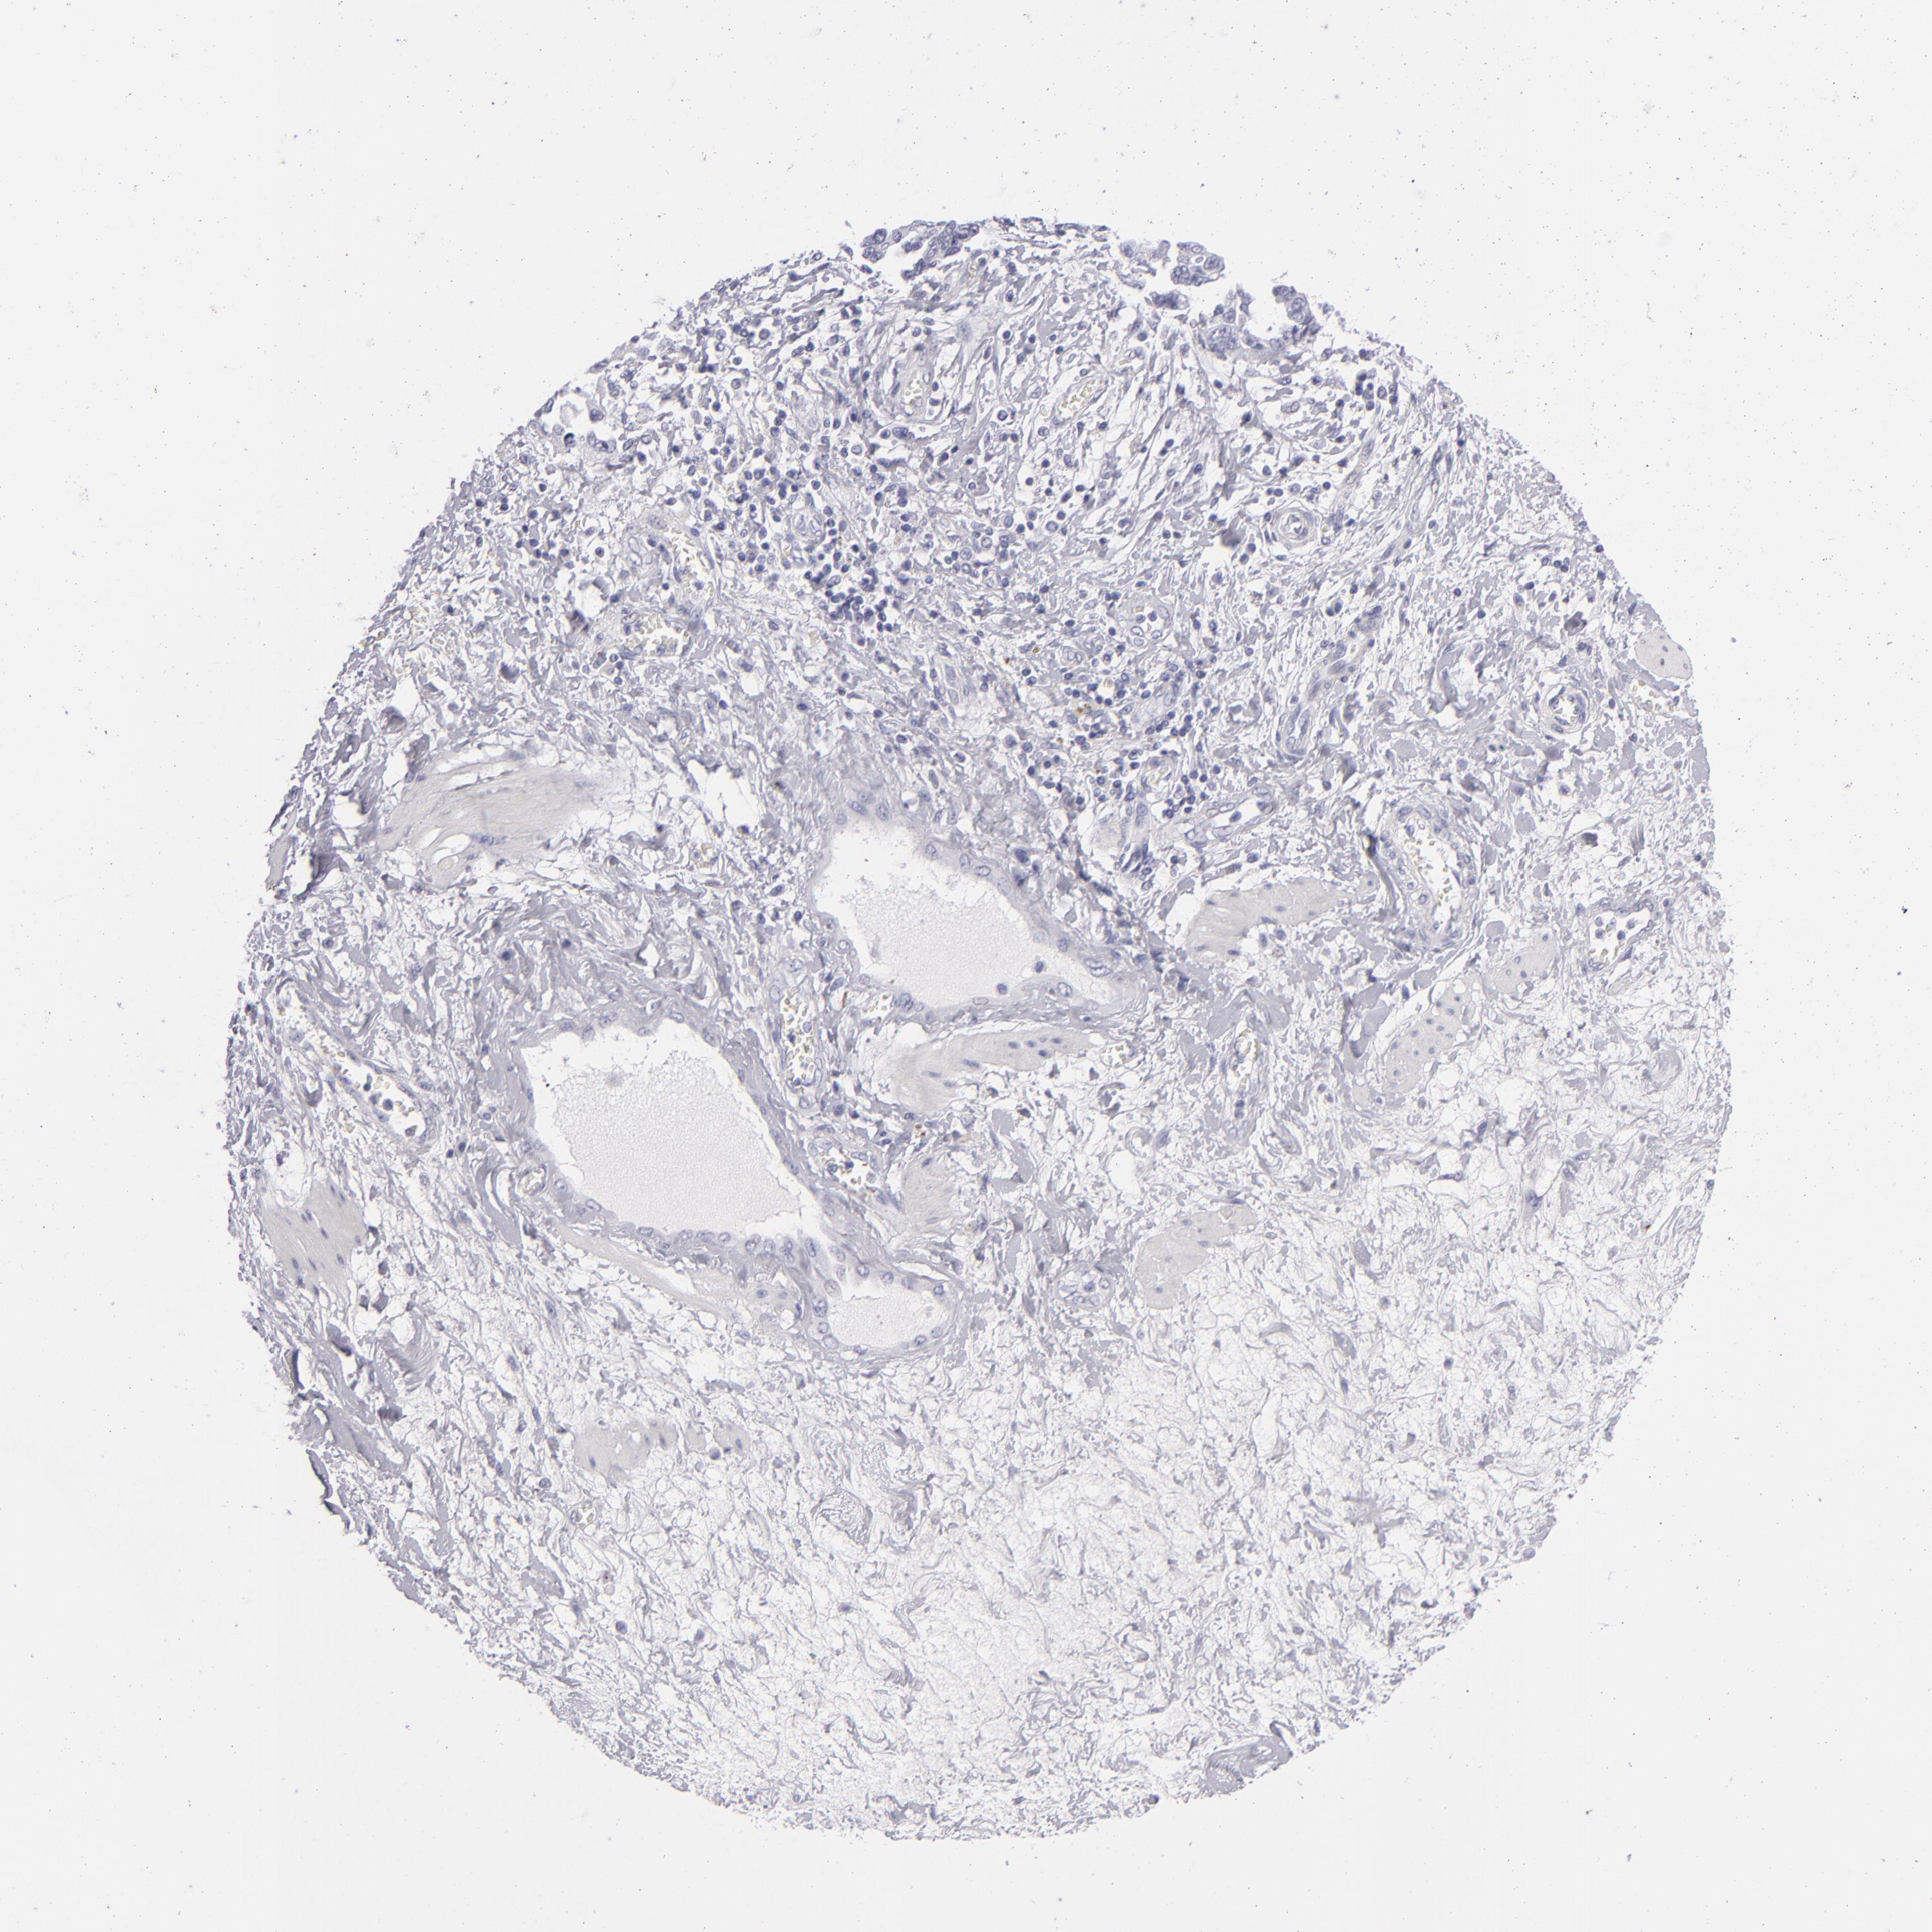

OVARIAN CANCER - Protein expressioni

A mouse-over function shows sample information and annotation data. Click on an image to view it in a full screen mode. Samples can be filtered based on level of antibody staining by selecting one or several of the following categories: high, medium, low and not detected. The assay and annotation is described here.

Note that samples used for immunohistochemistry by the Human Protein Atlas do not correspond to samples in the TCGA dataset.

Antibody stainingi

Antibody staining in the annotated cell types in the current human tissue is reported as not detected, low, medium, or high, based on conventional immunohistochemistry profiling in selected tissues. This score is based on the combination of the staining intensity and fraction of stained cells.

Each image is clickable and will lead to virtual microscopy that enables deeper exploration of all samples and also displays staining intensity scores, fraction scores and subcellular localization as well as patient and tissue information for each sample.

Antibody HPA006885

Staining

High

Medium

Low

Not detected

Cystadenocarcinoma, serous, NOS

Carcinoma, endometroid

Carcinoma, NOS

Cystadenocarcinoma, mucinous, NOS